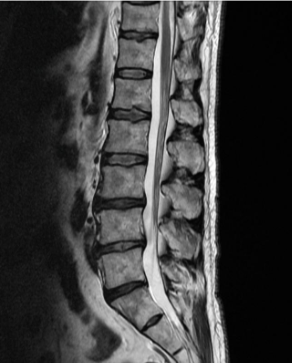

허리디스크는 디스크가 터져서 신경을 누를 경우 생기는 것으로 보통 4,5번에서 많이 발생하고 디스크가 터진 양이 적다면 터진 순간부터 수분이 날아가면서 양이 많이 없어지는데 그렇지 않고 양이 많을 경우 극심한 통증이 생깁니다.

허리디스크를 정확하게 진단하기 위해서는 엑스레이로는 힘들며, MRI를 통해 검사해야 정확하게 볼 수 있습니다.

MRI가 몸에 좋지 않지만 허리 통증으로 엑스레이만 진행할 경우 오진이 많아 지속적인 통증이 계속된다면 허리디스크를 의심하고 MRI 검사를 한번 받아보시길 권유드립니다.